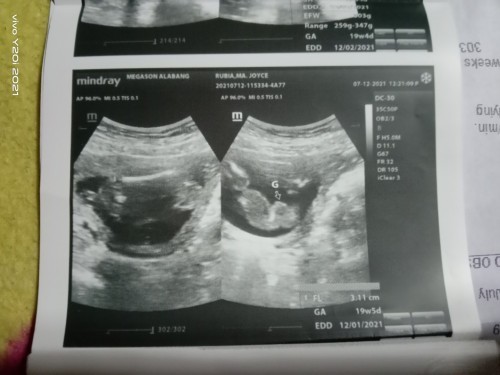

20weeks breech position🥺

Iikot pa kaya si baby? pang 2nd baby ko na to yung first baby ko naman po cephalic sya , ayoko kase ma cs kaya natatakot ako baka di sya umikot🥺 sana umikot na sya🙏🥺 btw nakita na po agad namin yung gender nya it's a GIRL🥺❤️